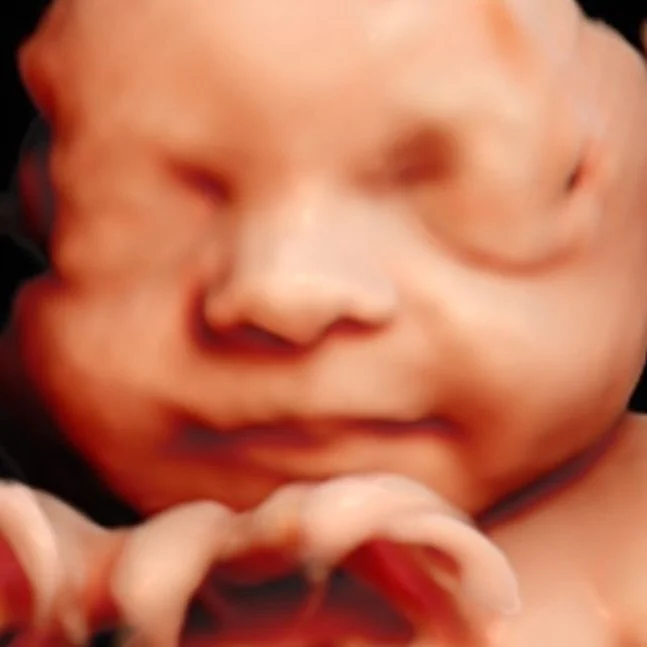

Established in 2014, Hello Baby 3D® has long been Australia's undisputed leader in non-diagnostic 3D|4D|5D pregnancy ultrasound.

I want you to bring your loved ones along to enjoy the experience! Pregnancy ultrasound offers you an amazing insight into what your little one is up to before they arrive in the world!

Hello Baby 3D® allocates the time that others don’t to ensure you receive the highest clarity, resolution, and definition images and video of your baby inside the womb.

We achieve this by using the highest grade ultrasound technology available, combined with my decade of expertise and personal commitment to achieve the best images possible.